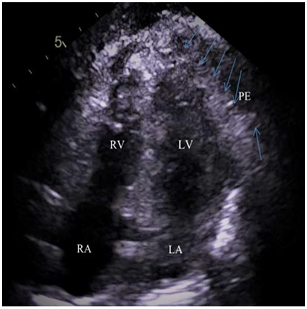

On initial examination, the patient was found to have borderline BP (SBP 101, DBP 60), diminished air entry at the bilateral right and left inferior lung fields. The cardiac examination was remarkable for normal S1, S2 and distended jugular venous distension of 10cm. Chest radiography (CXR) showed an intact esophageal stent along with radiolucent rim surrounding the cardiac silhouette (Figure 1). Echocardiogram (echo) revealed an air gap sign echoic dense space at the anterior and basal part of the heart consistent with the pneumopericardium with no signs of tamponade (Figure 2).  Computed tomography (CT) scan chest confirmed the presence of pneumopericardium in anterior pericardium along with left sided mediastinal pocket of air with foci of gas above the esophageal stent likely communicating with the pericardium (Figure 3). Given the clinical and radiological evidence of the symptomatic large pneumopericardium, we consented the patient on an emergency pericardiocentesis. Goals of care were discussed with the patient and his family and the patient opted interventional care measures. A following pericardiocentesis (with off label CT guidance) right sided parasternal approach (marked at the right 5th intercostal space with angulated entry projection of 70 degree medially with 27mm depth) was performed successfully with aspiration of 70ml of air followed with frothy blood-stained aspirate. The gentleman symptoms resolved immediately with picked up BP (SBP 123,DBP 67) and pigtail kept and secured in place for 5days without any complications.  Thereafter, a follow up echo and CT scan repeated and showed bright improvement in the clinical status (Figures 4 & 5) respectively.

Figure 2 2Dimension -4 Chamber apical view- showed air swirling (blue arrows) along with pericardial effusion (PE) in the pericardial cavity.